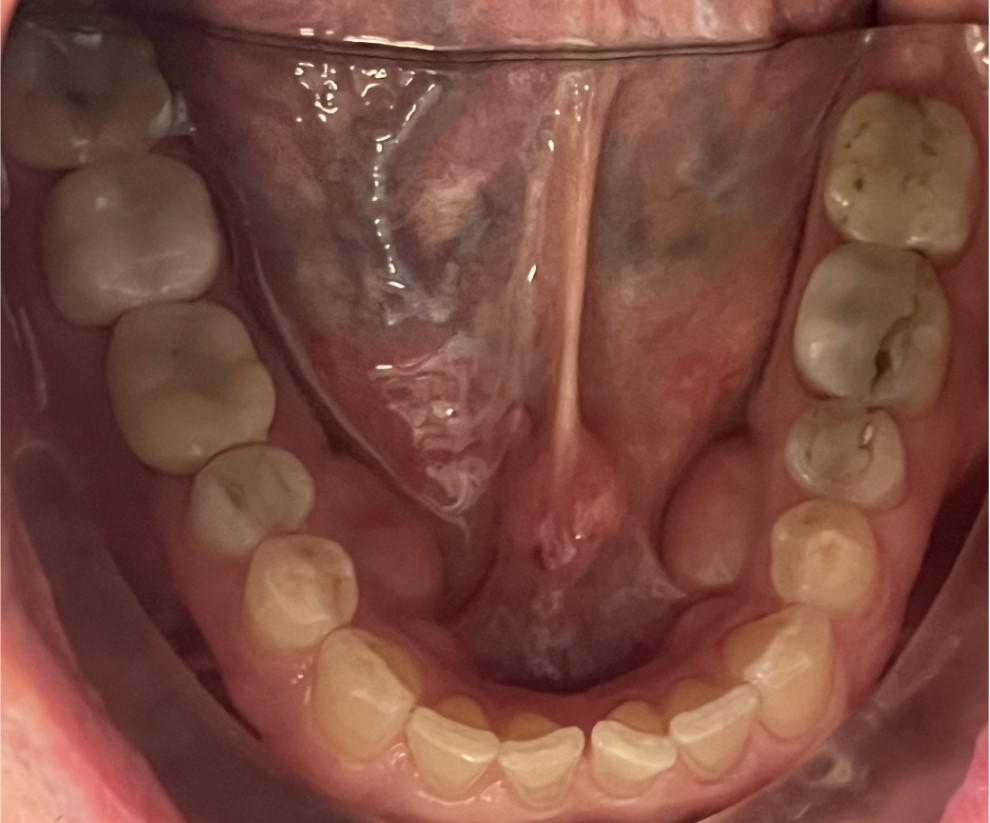

It does not matter whether teeth were lost through accident, disease or caries, dental implants are an excellent tooth replacement for many patients.

Dental implants can be used when:

- A single tooth is missing – Crowns

- Several teeth are missing – Bridges

- All teeth are missing – Bridges or dentures